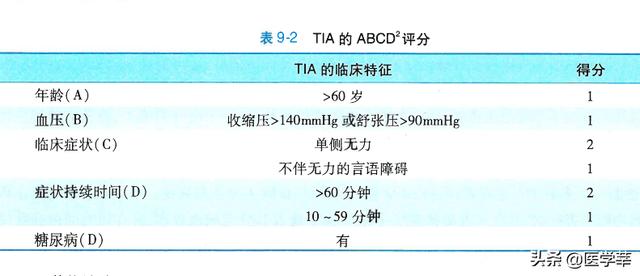

Bien que les symptômes des patients souffrant d'un accident ischémique transitoire disparaissent d'eux-mêmes sans lésion substantielle du tissu cérébral, le risque d'infarctus cérébral ultérieur est assez élevé. Après le début d'un accident ischémique transitoire, le risque d'infarctus cérébral est de 3,5 % au deuxième jour, il passe à 5,2 % au septième jour, à environ 8 % au trentième jour et à 9,2 % au quatre-vingt-dixième jour. Ainsi, le risque d'infarctus cérébral chez les patients souffrant d'ischémie transitoire ne diminue pas avec le temps, mais augmente plutôt en l'absence de traitement approprié, car la cause de l'infarctus cérébral n'est pas supprimée. Par conséquent, l'accident ischémique transitoire est appelé infarctus cérébral avec aura, et en raison du risque élevé d'évolution vers l'infarctus cérébral, dans une certaine mesure, il peut également être compris de cette manière : il s'agit d'un stade de lésion cérébrale ischémique différent de celui de l'infarctus cérébral. Certains d'entre vous se demandent peut-être comment évaluer le risque de développer un infarctus cérébral après la survenue d'un accident ischémique transitoire.

Plus la durée des symptômes et la gravité des symptômes cliniques après une ischémie transitoire sont importantes, plus le risque d'infarctus cérébral est élevé : les patients dont les symptômes durent plus de 60 minutes ont un risque plus élevé d'infarctus cérébral que les patients dont les symptômes durent de 10 à 59 minutes ; les patients présentant une faiblesse unilatérale des membres ont un risque plus élevé d'infarctus cérébral que les autres ; l'âge est également un facteur de risque d'infarctus cérébral, et le risque d'infarctus cérébral est plus élevé chez les personnes âgées de 60 ans et plus que chez les personnes âgées de moins de 60 ans ; les facteurs de risque cardiovasculaire tels que l'hypertension artérielle et le diabète sucré augmentent également le risque d'infarctus cérébral. Le risque d'infarctus cérébral est plus élevé chez les personnes âgées que chez les personnes de moins de 60 ans ; l'hypertension et le diabète sucré, qui sont des facteurs de risque cardiovasculaire, augmentent également le risque d'infarctus cérébral.